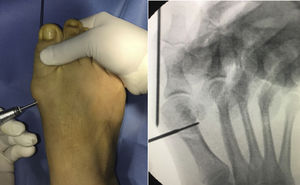

Se introduce una aguja de Kirschner de 2 mm subcutánea medial desde el extremo distal del hallux de manera retrógrada hasta la localización donde se realizará la osteotomía, en el cuello del primer metatarsiano.

A través de una incisión medial de 3 mm se realiza la osteotomía con una fresa tipo Shannon de 2 × 15 mm de largo, a nivel de la transición del cuello y la cabeza del primer metatarsiano. Se inicia el corte mediante un canal inicial paralelo a la superficie articular distal sobre el cuello del metatarsiano, que servirá de eje de la «v» y luego se completan las ramas a dorsal y plantar.

Se realiza el desplazamiento lateral de la cabeza, introduciendo la aguja de Kirschner endomedular desde la zona de la osteotomía con ayuda de una sonda acanalada.

Se fija la osteotomía de manera percutánea con dos tornillos a compresión de proximal a distal hacia la cabeza del metatarsiano. Cabe destacar que el primer tornillo colocado es el proximal, y este debe atravesar tres corticales a través de la osteotomía para una mejor fijación del tornillo (fig. 1).

Se procede a la liberación percutánea del tendón aductor. Se retira la aguja de Kirschner y se realiza vendaje correctivo en varo.

Se controla el procedimiento con radioscopia.